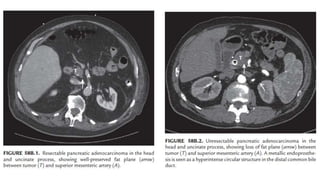

• Em seguida: TC helicoidal com contraste (realizada com a

conjunção de infusão IV de material de contraste)

– câncer de pâncreas: aparece na maioria das vezes como uma massa

pancreática hipodensa na fase venosa do contraste, com limites pouco

demarcados, dilatação da via biliar principal e vesícula biliar e

invasão/trombose de vasos adjacentes

– A TC também informa sobre as condições de linfonodos

peripancreáticos, estruturas adjacentes e do próprio fígado

– radiologistas experientes: especificidade para diagnóstico de tumores

pancreáticos de 95% ou mais

– sensibilidade: depende do tamanho do tumor, excedendo 95% para

tumores maiores que 2 cm de diâmetro